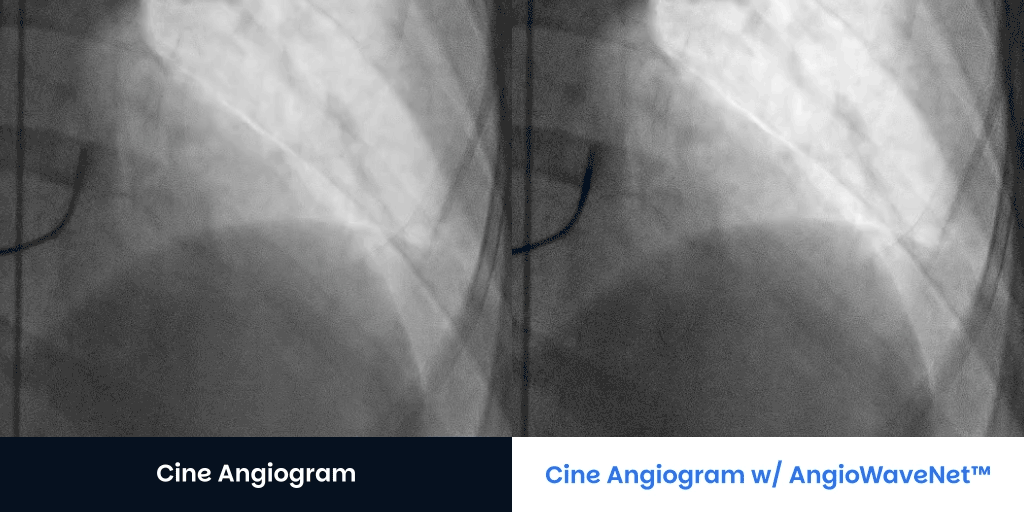

Large Patients BMI > 40 Contact UsGet a Demo CTO Patients Angiograms courtesy of:Jaikirshan Khatri, M.D., Hassan Saleh, M.D. and Weill Cornell Medical Center Left anterior oblique 27°, cranial 1° (unprocessed on left, processed on right) Left anterior oblique 31°, caudal 33° unprocessed on left, processed on right Right anterior oblique 2° caudal 33° (unprocessed on left, processed on right) Right anterior oblique 13°, caudal 36° unprocessed on left, processed on right Contact UsGet a Demo Diagnostic Cine Angiograms Contact UsGet a Demo